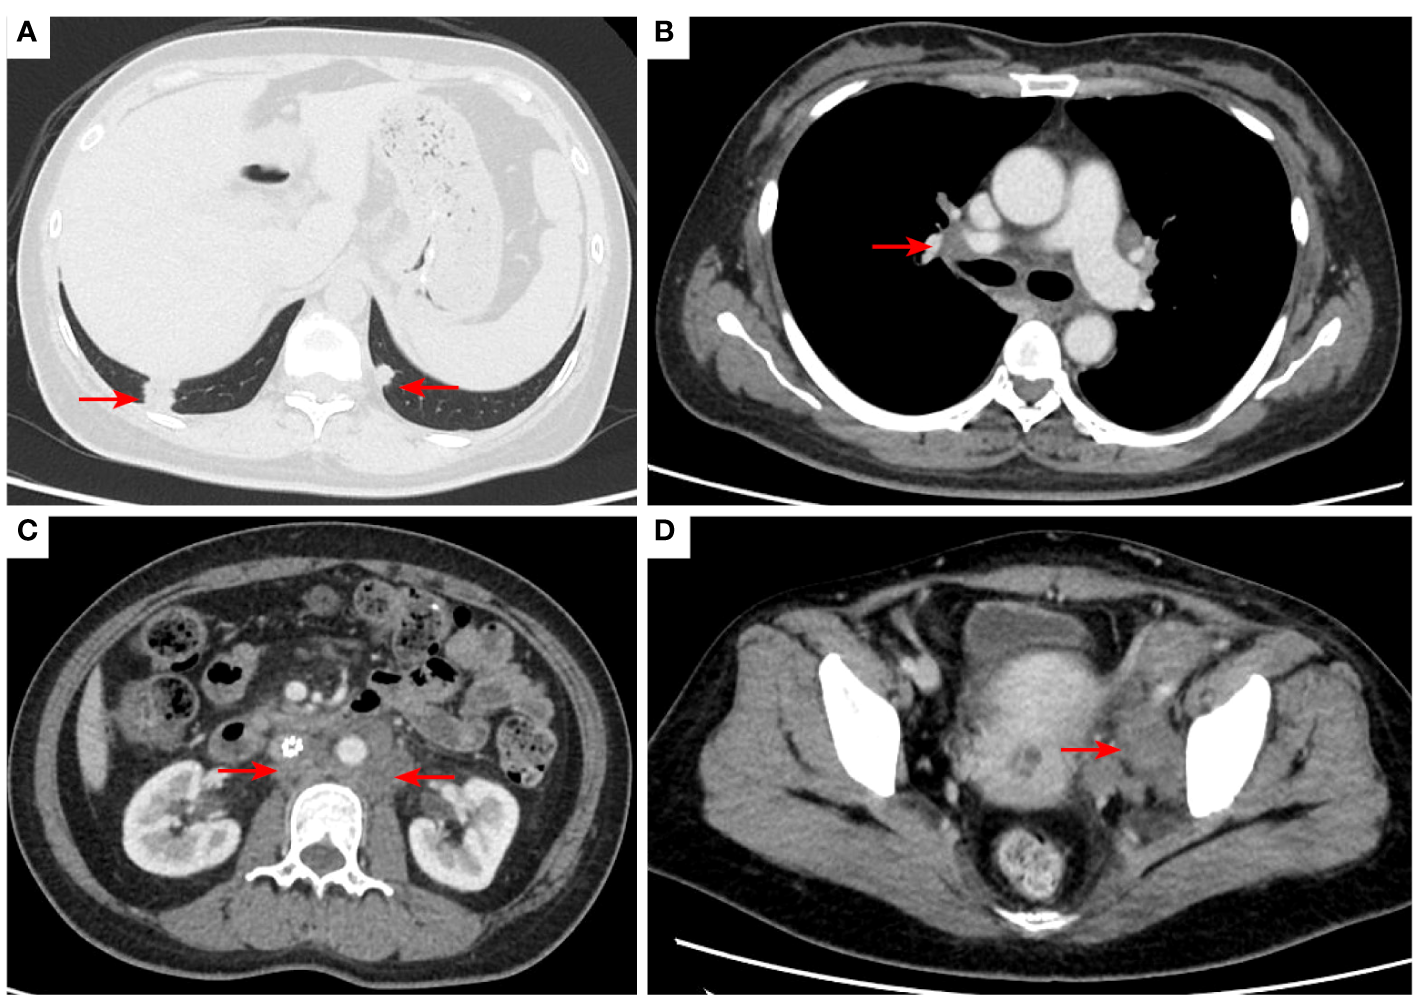

Figure 2

2020–7-10 CT scan: the metastatic tumor in the right lower lobe of the lung and the long diameter was 0.69 cm [red arrow, (A)]. Mediastinal lymph nodes were not significantly enlarged (B). Left acetabular metastases [red arrow, (C)]. Abdominal and abdominal lymph nodes were not significantly enlarged (D) No enlarged lymph nodes were found in the right hilum and the retroperitoneal area. The left pelvic lymph nodes were found and the short diameter was 4.05cm [red arrow, (E)].